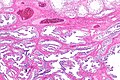

Adenomatous hyperplasia of the rete testis

Adenomatous hyperplasia of the rete testis. H&E stain. | |

| LM | epithelium with tubulopapillary or cribriform architecture separated by small amount of stroma |

Adenomatous hyperplasia of the rete testis (abbreviated AHRT), also rete testis adenomatous hyperplasia, is a rare benign lesion of the rete testis that may be confused with malignancy.[1][2]

- Epithelium with tubulopapillary or cribriform architecture separated by small amount of stroma.